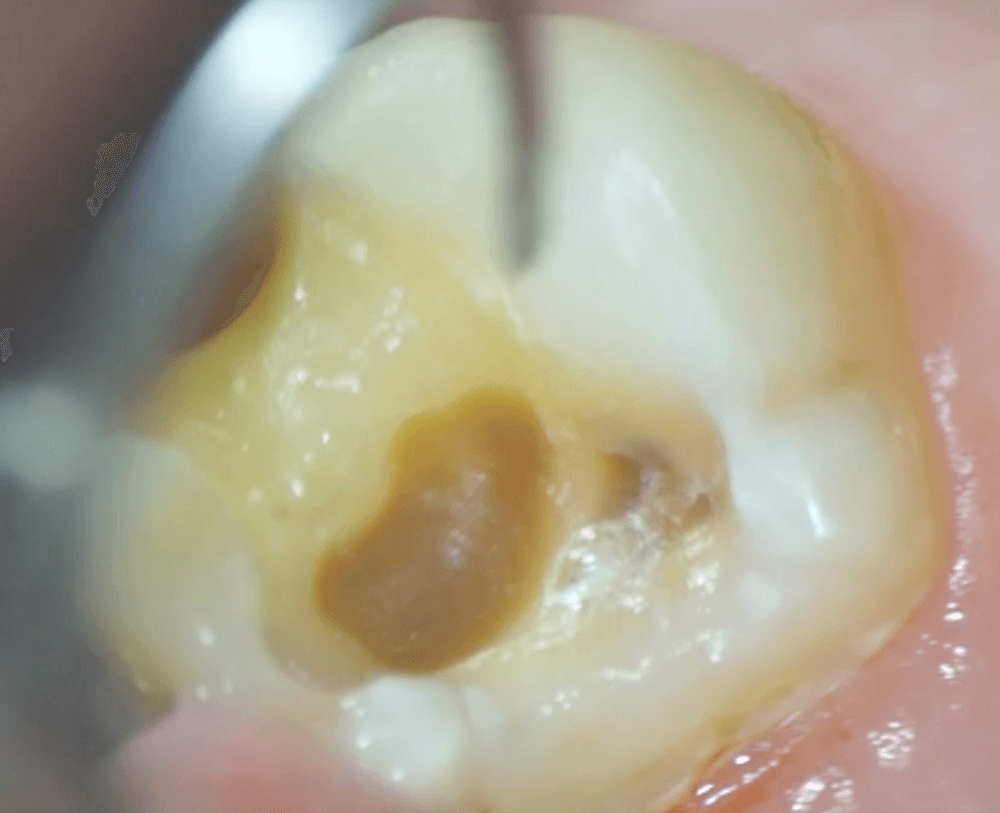

インレーが外れたあとに、内部を確認すると、土台となる材料がつまっていたため、これを取り除きました。

この土台の材料を取り除くと、その下には、なんと虫歯がありました。

中央の茶色の部分が虫歯です。つまっていたため、内部の状況がわかりませんでした。インレーを外さなければおそらく、もっと進行し、神経をもむしばんでいたかもしれません。このタイミングで、インレーを外して良かったです。

これが、虫歯を取りきったところの写真です。